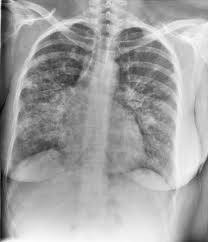

Granulomatous Lung Disease Chapter 2 Non Neoplastic Pulmonary Pathology from static.cambridge.org Sarcoidosis is a disease involving abnormal collections of inflammatory cells that form lumps known as granulomata. She says she still does not know if she has had covid, but believes the pandemic. Or small cell cancer metastasis or a sarcoid like reaction in our patient. Sarcoidosis is often identified as swollen hilar lymph nodes found in chest radiography during routine physical checkups. Secondhand smoke causes lung cancer in adults who have never smoked. By magdalena kegel | august 12, 2016. Sarcoidosis is a multisystem granulomatous disorder of unknown etiology that affects individuals worldwide and is characterized pathologically by the presence of noncaseating granulomas in involved organs. State of lung cancer report.

Frontiers Sarcoidosis As An Autoimmune Disease Immunology from www.frontiersin.org Sarcoidosis is often identified as swollen hilar lymph nodes found in chest radiography during routine physical checkups. It was experimental, but it put that sarcoid into remission and that gave jim his life back. Lung cancer, also known as lung carcinoma, is a malignant lung tumor characterized by uncontrolled cell growth in tissues of the lung. The cause of sarcoidosis is unknown. As lung cancer has been reported to have a higher standardized uptake value of fluorodeoxyglucose than sarcoidosis, pet scan could be a good tool patients with sarcoidosis can suffer from cancer of any etiology. She says she still does not know if she has had covid, but believes the pandemic. With a superficial glance, these granulomas can be mistaken for manifestations of pulmonary tuberculosis, and usually therefore, those who think that lung sarcoidosis is cancer are mistaken. Because sarcoidosis can escape diagnosis or be mistaken for several other diseases, we can only guess at how many people are affected.